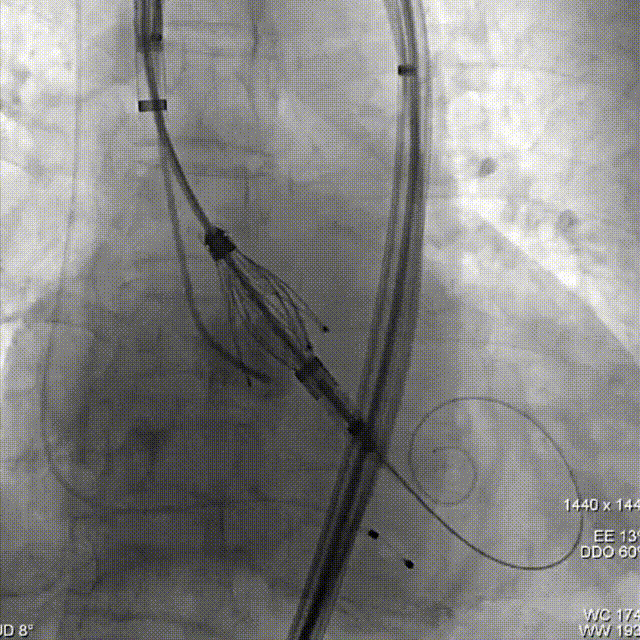

术中影像

瓣膜同轴调整

定位键与原生窦对齐

依次三窦内造影确认深度